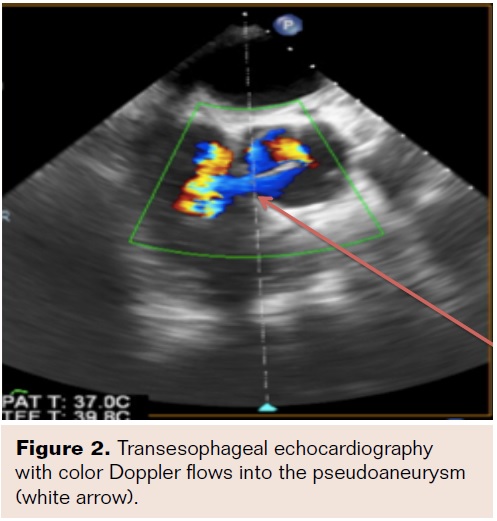

A 57-year-old male presented to his nearest hospital with acute onset of chest pain. His past medical history was significant for a type A aortic dissection repair with a 24 mm Dacron Hemashield graft (Maquet) 2 years prior and subsequent sternal wound infection requiring debridement. Afterward, he developed restrictive physiology and underwent a pericardial stripping via thoracotomy. Computed tomography (CT) scan revealed a large PSA (Figure 1) with a discrete and narrow entry point arising from the ascending aorta near the previous suture line that was confirmed by transesophageal echocardiography (Figure 2). The patient was transferred to our institution for further management. In light of his complex surgical history, a percutaneous transcatheter approach was chosen.